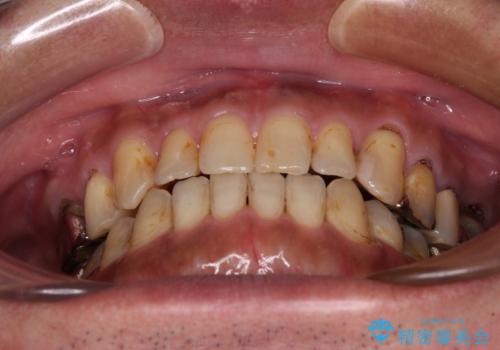

前歯の反対咬合をワイヤー矯正で改善して噛みやすく

- 咬み合わせの悪さを気にして来院された患者様です。

来院当初は、奥歯の銀歯が問題で咬み合わせが悪いと思っていらっしゃいましたが、前歯の反対咬合を改善することが最優先とご説明し、矯正治療を行うこととしました。

奥歯には抜歯が必要な歯があったため、事前に抜歯を行い、その後ワイヤー装置にて治療を開始しました。